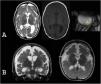

Macrocephaly is a clinical term defined as an occipitofrontal circumference more than two standard deviations above the mean. It is present in 5% of children and is a common indication for imaging studies. There are multiple causes of macrocephaly; most of them are benign. Nevertheless, in some cases, macrocephaly is the clinical manifestation of a condition that requires timely medical and/or surgical treatment. The importance of imaging studies lies in identifying the patients who would benefit from treatment. Children with macrocephaly associated with neurologic alterations, neurocutaneous stigmata, delayed development, or rapid increase of the circumference have a greater risk of having disease. By contrast, parental macrocephaly is predictive of a benign condition. Limiting imaging studies to patients with increased risk makes it possible to optimize resources and reduce unnecessary exposure to tests.